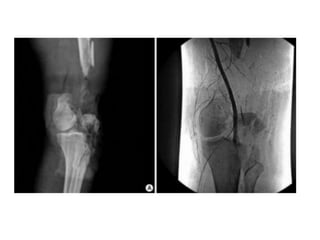

Imaging

Pre and post-reduction AP and

lateral of the knee

 look for asymmetric or

irregular joint space

 look for avulsion fxs (Segond

sign - lateral tibial condyle

avulsion fx)

 Osteochondral defects

• 26.

Imaging Pre and post-reductionAP and lateral of the knee  look for asymmetric or irregular joint space  look for avulsion fxs (Segond sign - lateral tibial condyle avulsion fx)  Osteochondral defects CT MRI